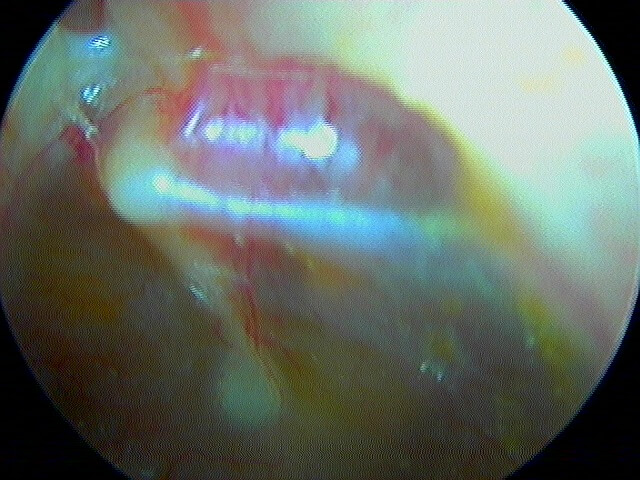

3/2 barotraumatique

– stade I : hyperhémie du manche du marteau et de la pars flaccida ;

– stade II : tympan rétracté, congestif, immobile

– stade III : aspect d'otite séromuqueuse

– stade IV : aspect otite séro-hémorragique, otohématome

– stade V : perforation

Ici des stades V perforés